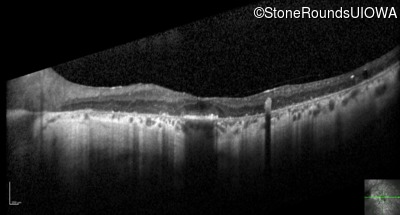

Visit at age: 38 years

Optical Coherence Tomography - Left - 20/70

Exemplar / OCT Stack

OCT Stack